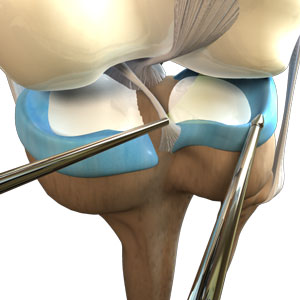

Partial Arthroscopic Meniscectomy

Partial arthroscopic meniscectomy is a procedure to remove the damaged part of a...

Meniscectomy

Meniscectomy is a surgical procedure indicated in individuals with torn meniscus where...

Know More -

Partial Meniscectomy

Partial meniscectomy is a surgical procedure to remove the torn portion of the meniscus from...

Know More -

Meniscal Surgery

Meniscal surgery is a surgical procedure employed for the treatment of torn or damaged...

Know More -